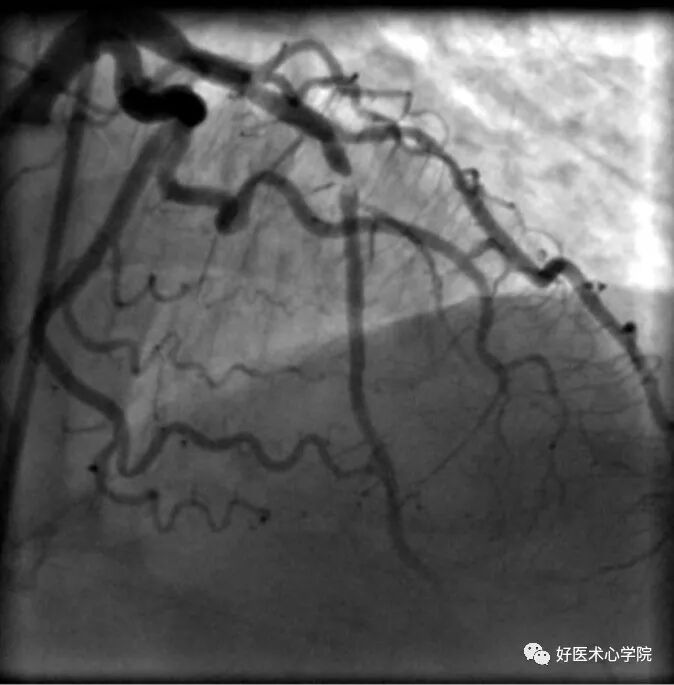

右前斜位:观察右冠近中段的体位。

造影导丝是什么珍藏 冠脉造影从流程到诊断,基础必备!_https://www.jmylbn.com_新闻资讯_第55张